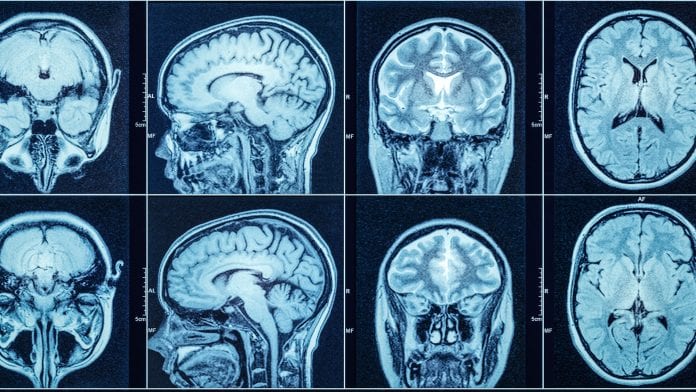

Let me start with what MRI stands for: Magnetic resonance imaging.

Doctors send patients in for MRI’s for all kinds of health concerns things like organs and the depth of bones can be scanned. They can see very deep details of things like nasal cavities to the whole brain. MRI’s can be used to detect if someone has abnormal tissue or a blockage in their veins. It can even be used to see the capillaries in the brain! I don’t know the medical science behind MRI’s but they can give layered information about the body. The radiologist will look at it and give a report to the doctors. Sometimes the specialist will look too.